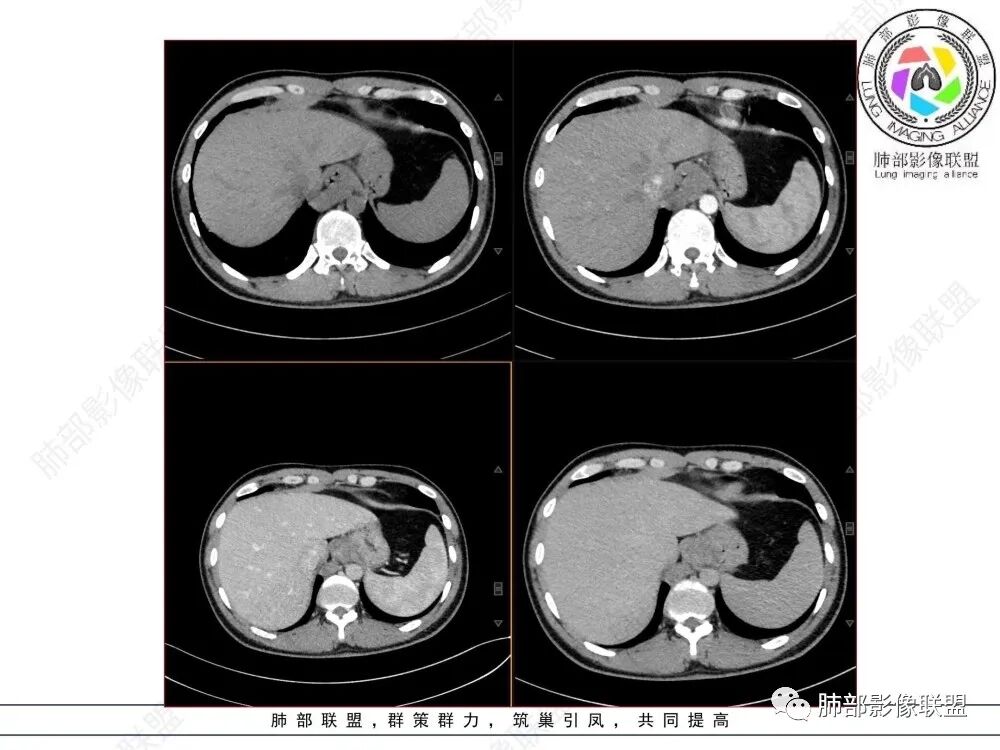

年轻男性,食管下段占位性病变长轴平行于食管,平扫密度尚均匀,增强轻度强化,MRI示T1、T2低信号,DWI低信号。考虑来源于食管,考虑平滑肌瘤或神经鞘瘤>间质瘤

定位后纵膈,这个位置,神经,淋巴,食管,轻微强化,T2低信号,弥散受限,考虑平滑肌瘤,鉴别神经原性。

平滑肌瘤(食管下段团块状肿块,环食管生长,分叶密度均匀,增强轻度强化。钡餐时食管受压移位,T1 T2 DWi低信号,病变来源于食管,考虑平滑肌瘤)

定位后纵膈,实性密度,增强轻度强化,T1等低信号T2低信号,弥散未受限。钡餐造影,食道及贲门管壁柔和,造影剂通过顺畅。考虑神经鞘瘤。鉴别食道平滑肌瘤。

轻度强化,等T1等T2,弥散不受限,密度及信号相对均匀,感觉后壁来源并食管受压推移,考虑平滑肌瘤。

影像学特点:类纵隔区病变,沿食管生长,形态不规则,但边界清楚,内部信号/密度均匀,强化程度比较弱。

影像诊断思路:起源食管肿瘤(非黏膜起源,肌层起源),良性或低度恶性肿瘤可能性大,一般以神经鞘瘤、胃肠间质瘤及平滑肌瘤为主。食管神经鞘瘤强化明显均匀、以食管上段多见,周围常见炎性增大淋巴结,不太符合;胃肠间质瘤小的比较均匀,大的不均匀,但强化程度较高;影像上看这例病例比较符合平滑肌瘤。

T2低信号是关键,提示平滑肌细胞

食管平滑肌瘤是最常见的食管良性肿瘤,多见于男性,男女之比为2.6:1,高发年龄 30~60岁之间与食管癌相比,食管平滑肌瘤 的一个主要特点是病史相对较长,病情进展缓慢。病史最长者达10年余,平均 15.7个月,尽管病史较长,但大多数患者仍能进普食。食管平滑肌瘤的诊断一般比较容易,结合患者临床症状、食管造影及食管镜所见,一般均能得出正确诊断。食管造影主要为充盈缺损,病变与食管壁成锐角,粘膜线连续无破坏,管腔收缩扩张比较自如。钡餐造影敏感性高,但对食管壁间及食管周围情况难以判断。CT具有极高的密度分辨率,并且可以获得高质量的多平面重组图像,有利于食管壁间及食管周围情况的判断,表现为食管下段环绕管壁生长,偏心性或薄厚不均软组织密度肿块,密度均匀,内缘分叶状,管腔与正常食管壁构成不规则多角形扩张,增强动脉期无强化,多角度重建其病灶长轴与食管长轴不一致。由于食管壁在收缩状态下厚度约为5.6mm,扩张状态厚度不超过3mm,CT扫描时保持食管处于扩张状态可提高小病灶检出率。MR表现为T1加权等信号,T2加权稍高信号,可见高信号粘膜层,增强扫描轻度渐进性强化,密度均匀,无出血坏死。对于粘膜及周围脂肪间隙的判断具有明显优势。